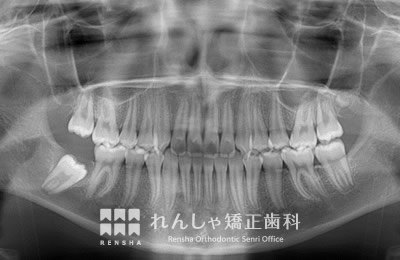

右下7番目(12歳臼歯)がなかなか出てこないため、6歳臼歯を支えに引っ張り出しました。

治療前

| 主訴 | 前歯のがたつき |

|---|---|

| 診断名 | Angle Class I 叢生 |

| 初診時年齢 | 10歳10か月 |

| 装置名 | 舌側弧線装置 |

| 抜歯非抜歯 | 非抜歯 |

| 治療期間 | 3年10か月 |

| 費用の目安 | 約36万円+消費税(検査料金、都度の処置費用等も合わせた総額) |

| リスク副作用 | 歯の移動に伴う軽微な歯根吸収、歯槽骨吸収、歯肉退縮(いずれも本症例ではほぼ無し)、矯正器具装着中のカリエスリスク増大(本症例ではカリエス発生無し) |